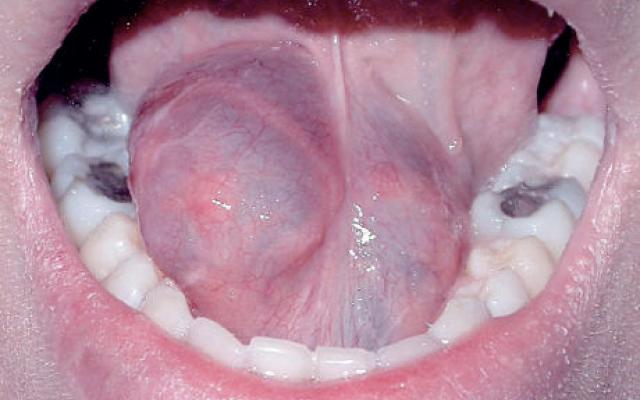

Diagnose in beeld (347). Een man met een zwelling onder zijn tong

Een 23-jarige man meldde zich met een pijnloze, progressief toenemende zwelling onder zijn tong. Door de omvang van de afwijking ging het slikken moeizaam. Bij onderzoek werd een forse, fluctuerende zwelling rechts op de mondbodem gezien, met uitbreiding over de mediaanlijn (figuur). De diagnose luidde ‘ranula’; dat is een verwijding van de afvoergang van de sublinguale speekselklier met ophoping van speeksel. De ranula is een mogelijk gevolg van trauma. De naam verwijst naar de kikkerblaas (Latijn: rana = kikker; ranula = kleine kikker). De ranula zit craniaal van de mondbodemspier, de M. mylohyoideus. Indien de zwelling zich…